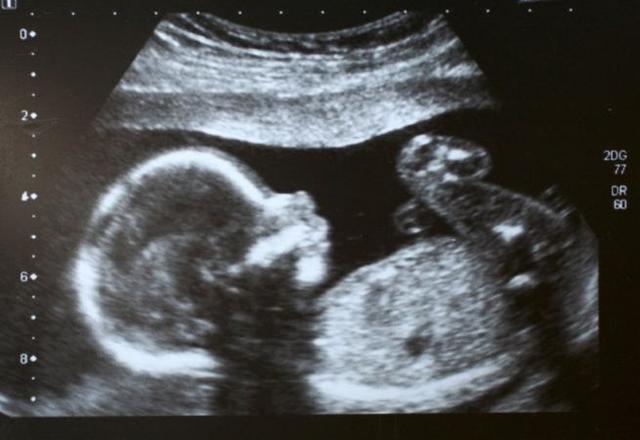

Semana 11 a 14

Los párpados del bebé se cierran y no volverán a abrirse hasta que más o menos la semana 28.

La cara del bebé está bien formada.

Las extremidades son largas y delgadas.

Aparecen las uñas en los dedos de las manos y los pies.

Aparecen los genitales.

El hígado del bebé está produciendo glóbulos rojos.

La cabeza es muy grande -- aproximadamente la mitad del tamaño del bebé.

Ahora su pequeño puede formar un puño.

Aparecen brotes dentarios para los dientes del bebé.